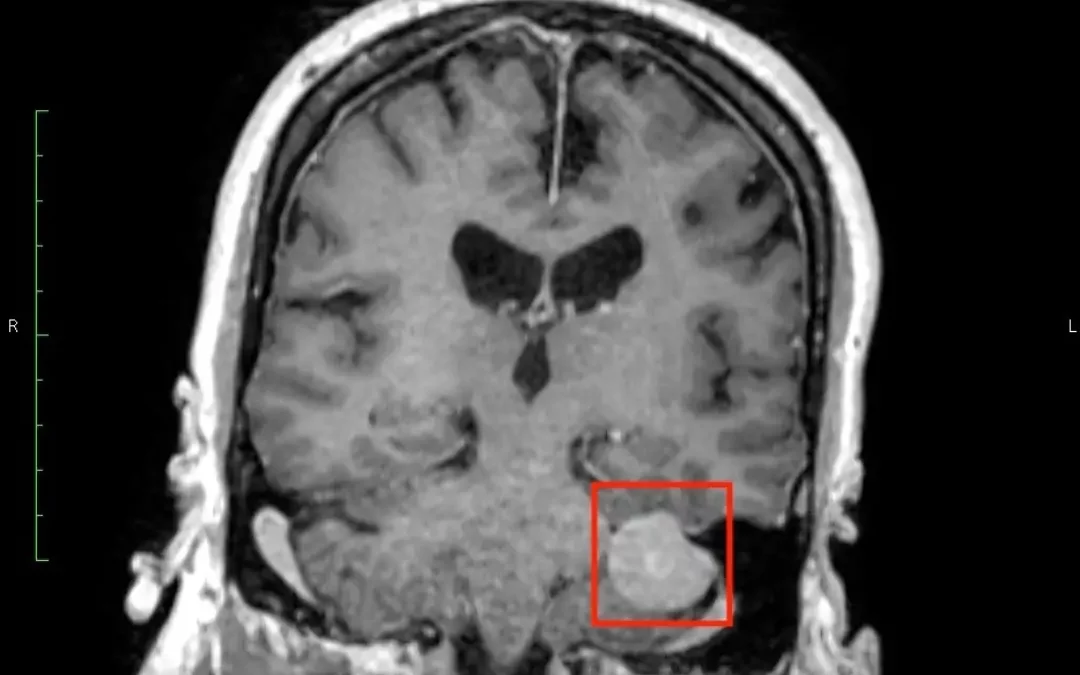

So. This is my brain. That little highlighted blob? Not decorative. There was a tumor sitting on my cerebellum — the part responsible for things like balance, coordination, and generally moving through life like a functioning human. See all the space it was...